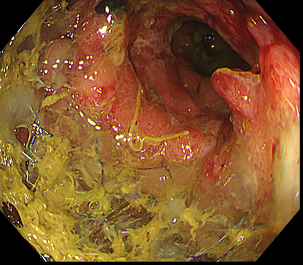

消化管の狭くなっている部分に対してステント(筒のようなもの)を挿入し狭窄部を広げる治療になります。

主に癌などの悪性腫瘍の狭窄に対して行う治療で、切除不能狭窄の症状緩和目的や腸閉塞症状を伴う狭窄の緊急手術回避目的で行います。